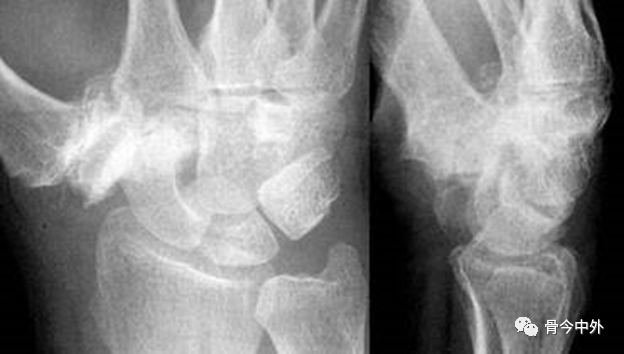

图34

1.舟骨和尺骨茎突骨折。

2.掌骨弧线Iand II 在月骨-三角骨间隙中断。

3.月骨和舟骨近极、桡骨平行关系不存在。

4.舟骨缩短提示其向掌侧倾斜。

5.其他掌骨平行关系存在。

6.诊断:可能为月骨周围脱位(仅从PA位难以判断月骨或月骨周围脱位);月骨呈三角形提示月骨倾斜或脱位伴倾斜。